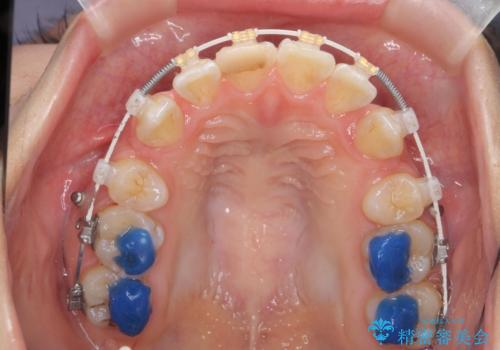

突き出た前歯を治したい 小臼歯抜歯+マルチブラケット矯正

- 突き出て、気になる前歯の角度の改善を求めて来院されました。

前歯の角度を改善するために小臼歯4本の抜歯を行いワイヤー マルチブラケットを用いて、しっかりと前歯の角度を改善する治療計画としました。